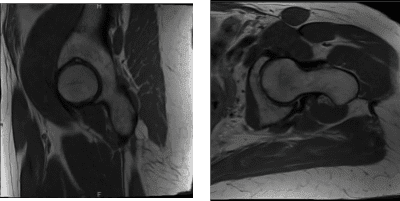

She presented MRI results for both of her hips that showed mild common hamstring tendinosis with a small intrasubstance tear and surrounding edema at the ischial tuberosity. Extensive avascular necrosis of the right femoral head. Degenerative changes in the lower lumbar spine for her left hip.

Extensive avascular necrosis involving the majority of the right femoral head and surrounding bone marrow edema extending into the femoral neck. Crescentic subchondral fracture line is seen medially without articular collapse or fragmentation.

There are mild osteophytic changes of the right femoral acetabular joint and a moderate joint effusion. Mild gluteus minimus tendinosis without a tear, for the right hip.

MRI Left hip non-contrast

MRI Right hip non-contrast